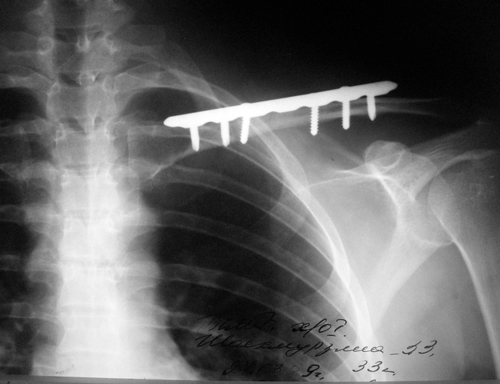

О особенно тяжелых случаях, когда обычная повязка при переломе ключицы уже не поможет, потребуется хирургическое вмешательство, которое применяют чаще всего именно из-за повреждений нервов и сосудов, либо при наличии риска повредить их при вправлении отломков костей.

Лечение перелома ключицы может варьироваться в зависимости от типа и степени тяжести травмы. В большинстве случаев применяется консервативный метод, включающий иммобилизацию с помощью повязки или шины. В более сложных случаях может потребоваться хирургическое вмешательство для восстановления правильного положения костей и их фиксации с помощью металлических пластин или винтов.